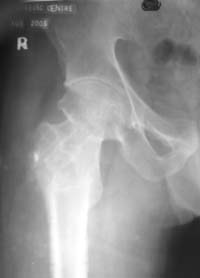

Глубокоуважаемые коллеги,Вчера обратился мужчина 31 г. Травма 2 месяца назад, лечился в одном из городов области. Был не самый тяжелый перелом таза, который проведен консервативно. С ним и связывали невозможность поднять ногу.

Однако на сегодняшнем снимке обнаружился перелом шейки бедра. Больной уже ходитс частичной нагрузкой. Учитывая срок и картину на снимке, что предпринять? У нас предложены варианты 1)не оперировать, 2)закрыто 2 спонгиозных винта, 3)вальгизирующая остеотомия. Эндопротез как-то даже в список включать пока не хочется. Какие есть соображения? Что из перечисленного или что-то другое выбрать и почему? Заранее спасибо.

Dear colleagues,A male 31 years old treated elsewhere after not severe pelvic fracture, was managed non operatively. So the injury looked as a reason of his inability to elevate the leg. However at the recent x-rays the neck fractire was found. The patient already has been walking with partial weight-bearing.Looking at the x-rays and the time since the injury, what is the optimal treatment for now? We discussed 1)leave as is, 2)2 cancellows screws as is, 3)valgus osteotomy. Total hip replacement looks unnecessary yet.What is your opinion? Which option from the listed or something else should be preferred and why?THX in advance.